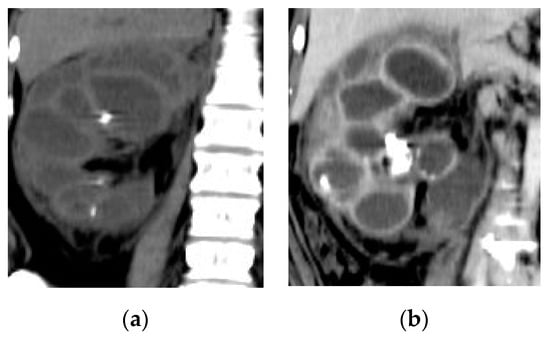

2.3. Pyonephrosis

| Pyonephrosis | Dilated thick-walled hyperenhancing collecting system, distended with high attenuation pus-filled fluid, fluid—fluid layering at T2WI, and thinning of the renal cortex. |